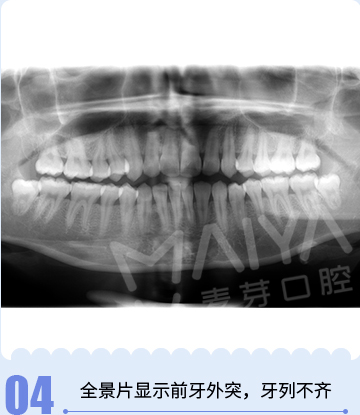

牙齿症状:牙列不齐,上下颌前牙前突